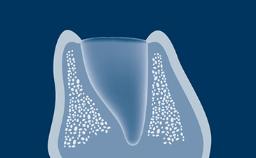

种植治疗是否成功受多个因素影响。这些因素包括种植治疗手术方面的基本要求。本模块将重点介绍一般口腔手术和外科种植手术的翻瓣设计基本原则。目的是确保在具有足够可见性和术区通路的情况下,尽可能无创伤地执行手术。

- 描述翻瓣设计的原则

- 描述种植手术的翻瓣设计原则

- 指出针对种植手术中特定情况的翻瓣设计